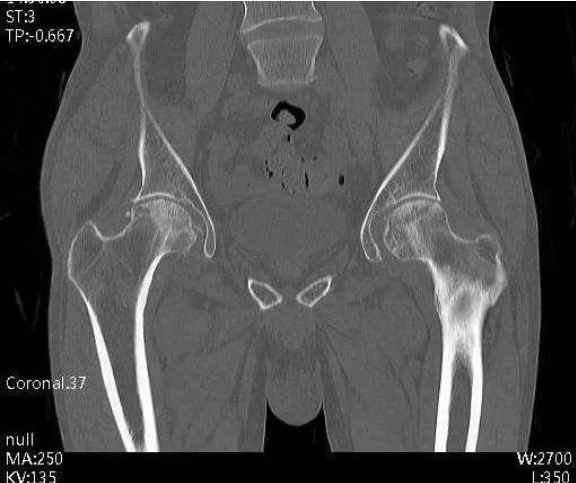

入院后,通过完善X线片、三维CT、MR等相关检查。发现周先生双侧股骨头坏死,尤其右侧股骨头严重变形,相关检查结果提示周先生的股骨头坏死已非常严重,双侧均达到Ficat分期Ⅳ期,右下肢较对侧缩短2cm。双侧髋关节旋转活动受限,右侧髋关节活动受限较重,双侧“4”字试验(+)。

术前CT